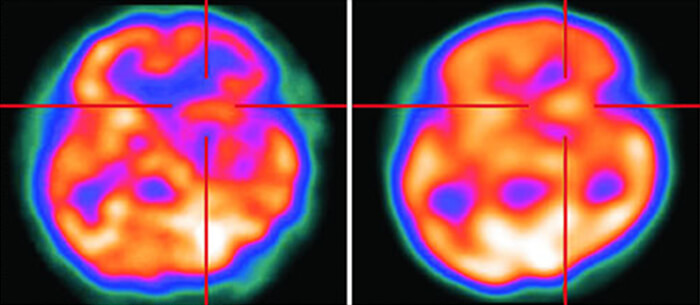

Perfusion Computed Tomography is a noninvasive imaging technique that provides quantitative evaluation of the brain (Cerebral Perfusion), by generating maps of Cerebral Blood Volume (CBV), Cerebral Blood Flow (CBF), and Mean Transit Time (MTT). Brain Perfusion CT is mainly used for the diagnosis of cerebral ischemia, the evaluation of vasospasm, and the assessment of regional perfusion following a severe head trauma. This article is accredited by the ASRT for 1 Category A CE Credit and provides a general overview of Brain Perfusion CT, including image acquisition, data processing, technical limitations, and major clinical applications.

Brain perfusion CT is a Computed Tomography technique that is used to provide detailed information about the blood flow in the brain vessels. This technique is primarily used for clinical diagnosis cases like ischemic stroke, Trauma, brain cancer, and many other diseases.